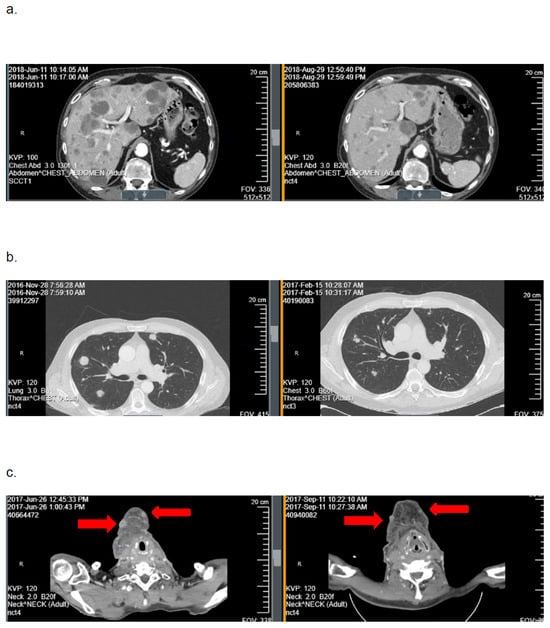

In cohort A, the ORR was 9.1% (95%CI: 0–19.4). Best tumor response included PR in 3 patients (9.1%), SD in 10 (30.3%), and PD in 20 (60.6%). One response was confirmed and two responses were unconfirmed (Figure 2). As seen in Figure 3, the depths of these partial responses were significant. The DoR’s were 2.3, 2.5, and 4.5 months. In cohort B, the ORR was 0%. The best tumor response included SD in three patients (25%) and PD in nine (75%).

Figure 2.

Representative examples of computed axial tomography imaging scans obtained at baseline (left) and after two cycles of mitomycin-C (right) from the three patients on cohort A with a tumor response with mitomycin-C: (a) patient 21: hepatic metastases, (b) patient 10: pulmonary metastases, and (c) patient 14: subcutaneous metastases.

In this trial, the primary hypothesis of achieving an ORR of ≥30% with mitomycin-C was not met in either cohort. The ORR was 9.1% among patients with HPV-positive, platinum-refractory RM-HNSCC (cohort A) and 0% among patients with HPV-negative, platinum-refractory disease (cohort B). Although three patients in cohort A experienced deep tumor responses with mitomycin-C (Figure 2 and Figure 3), the DoRs were brief (≤4.5 months). Based on these data, further investigation of mitomycin-C as monotherapy in patients with biomarker-unselected, platinum-refractory RM-HNSCC is not warranted.